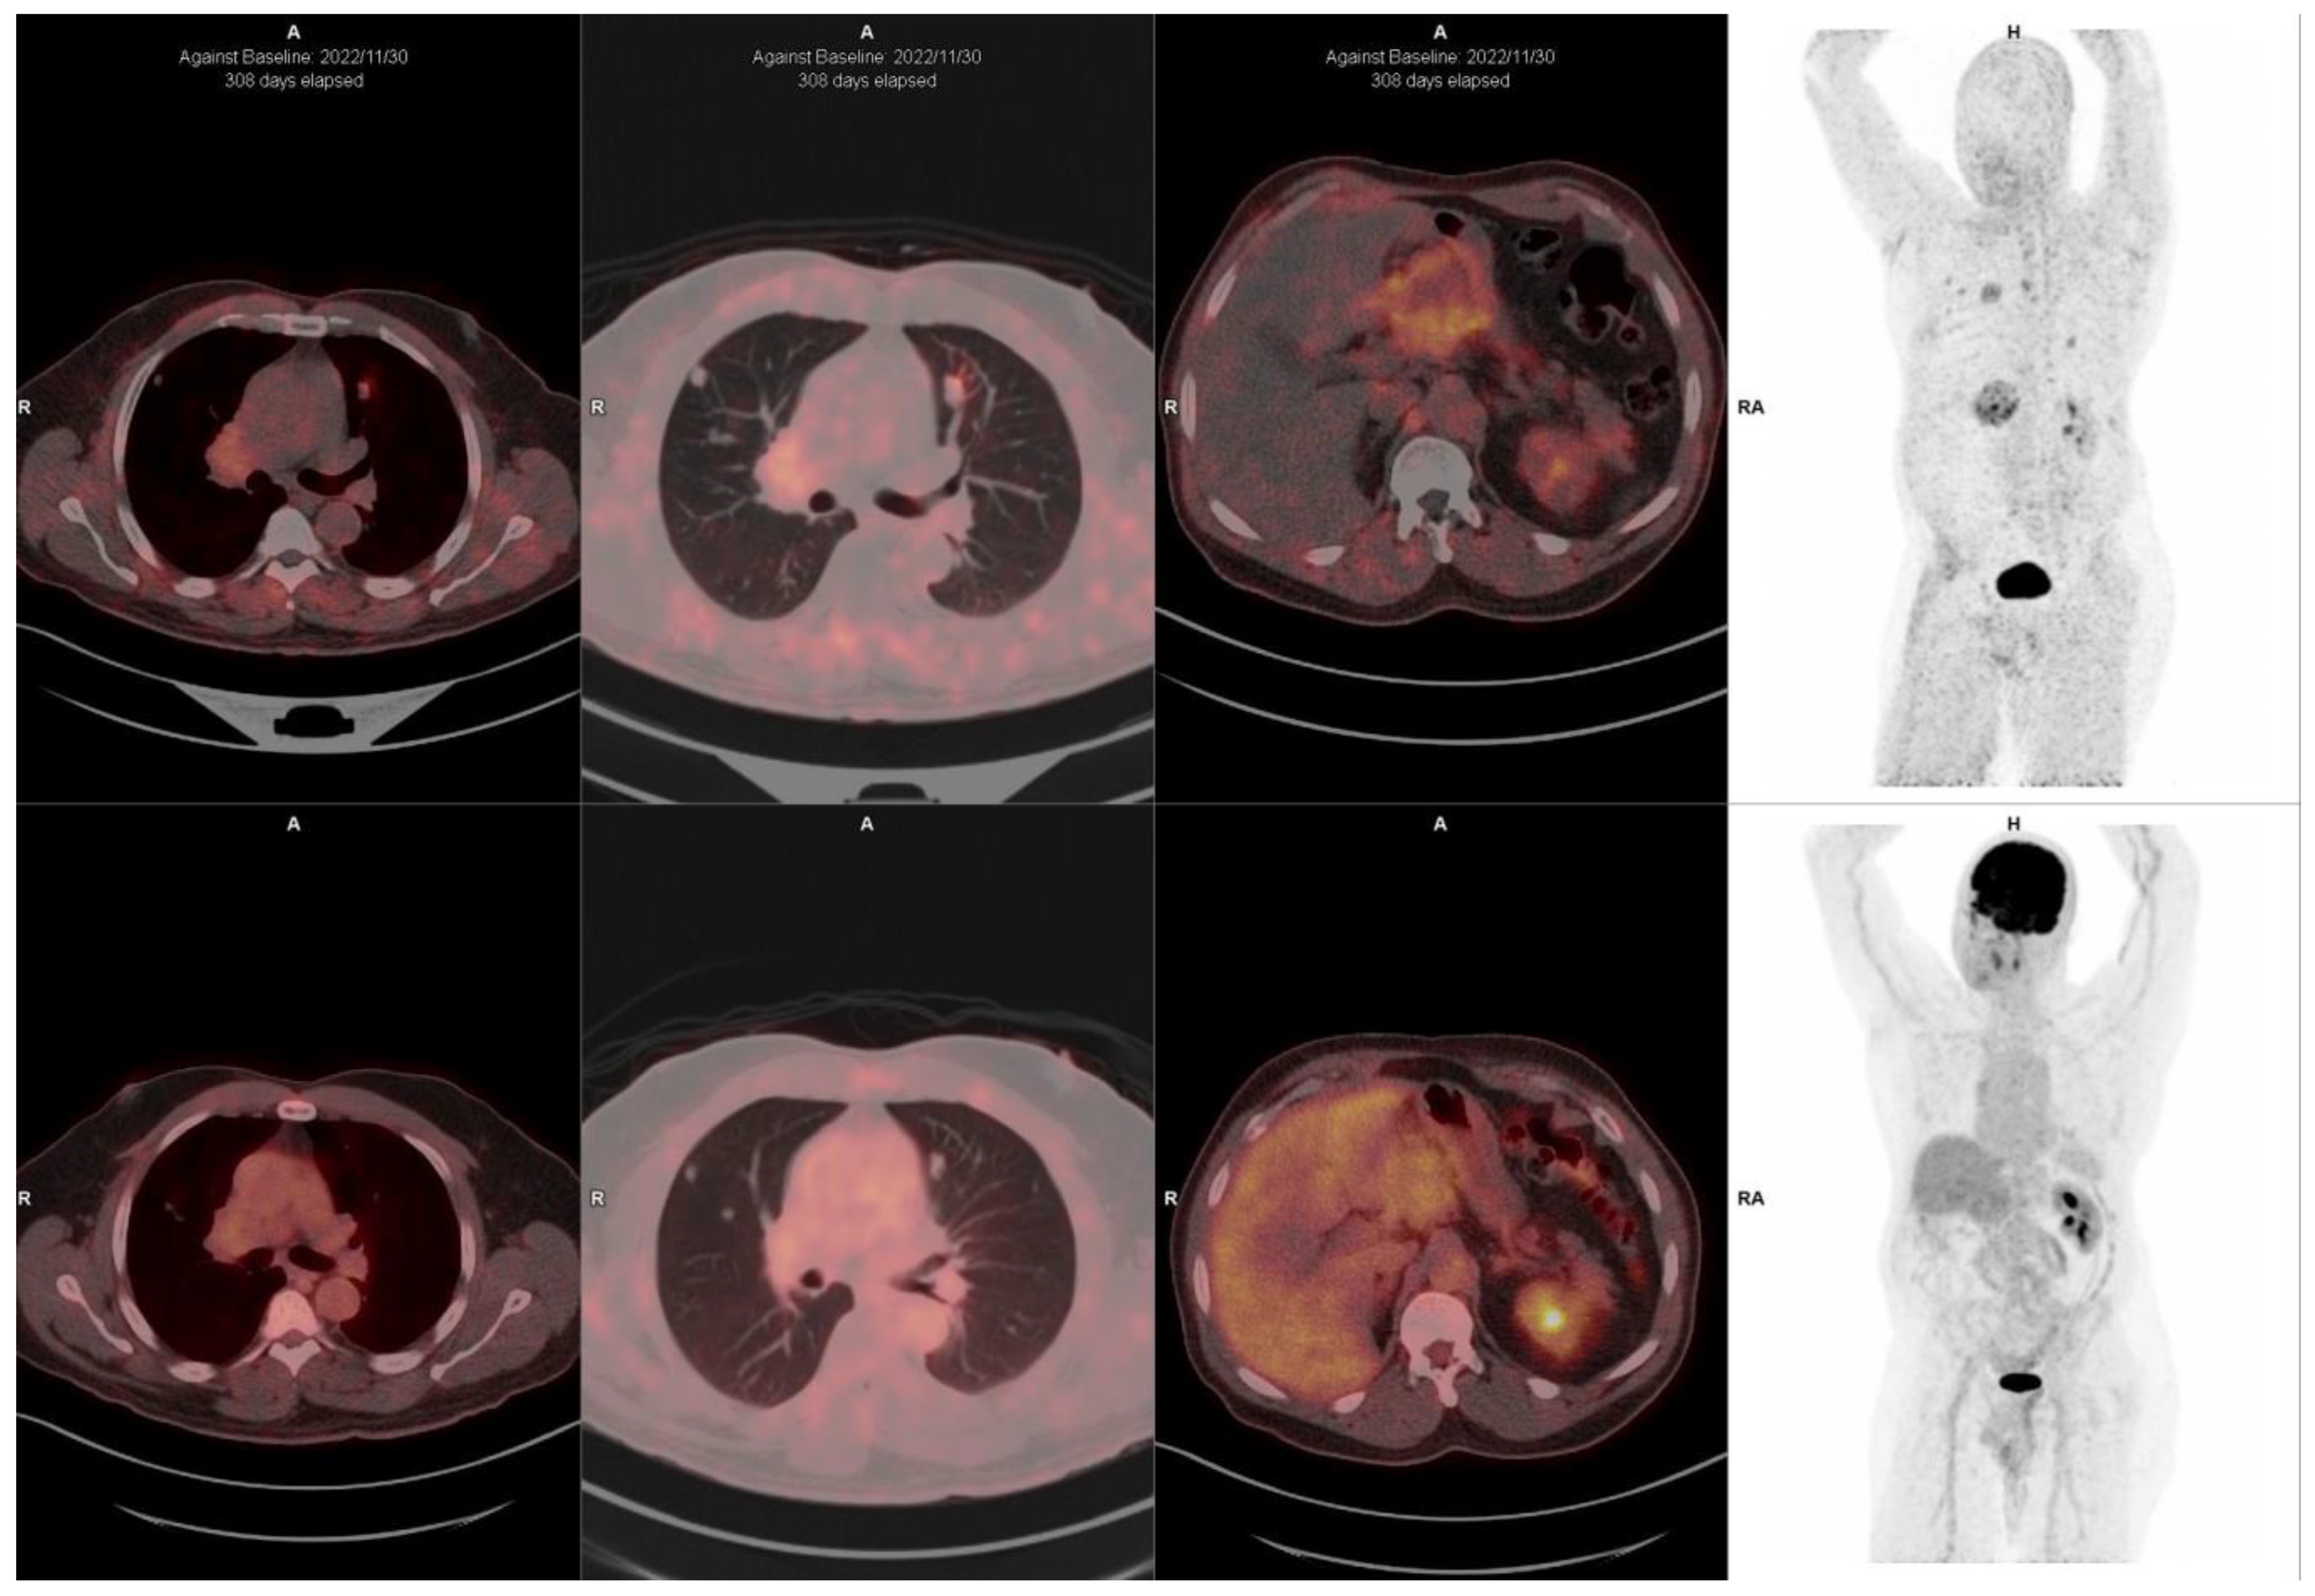

10. FAPI-Based Theranostic Approaches

11. Challenges and Limitations in FAPI Therapeutic Approaches

12. The Potential Role of FAPI PET-Based Theranostic Approaches